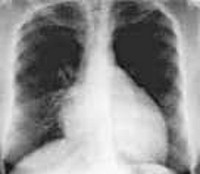

Рентгенография органов грудной клетки выявляет значительное увеличение размеров сердца, признаки венозного застоя в легких. Эхокардиография позволяет исключить другие причины сердечной недостаточности (амилоидоз сердца, врожденные пороки сердца и пр. ); обнаружить перикардиальный выпот, дилатацию полостей сердца, гипертрофию миокарда, внутриполостные тромбы; оценить подвижность и толщину стенок.